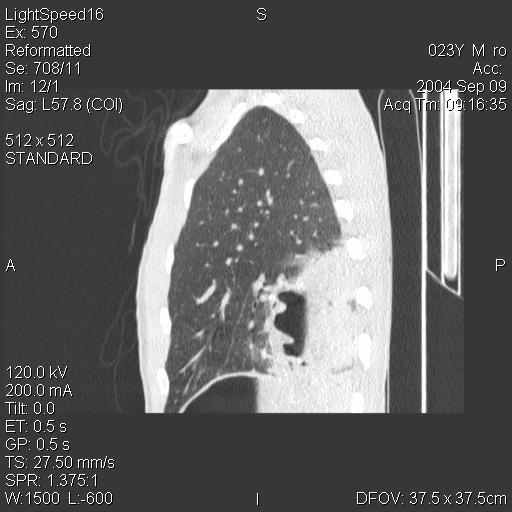

Рис. 2. Рентгенограммы и компьютерные томограммы больного Ш., 31 г. после клапанной бронхоблокации.

При контрольном рентгенологическом исследовании слева определяется ателектаз сегментов базальной пирамиды в виде треугольной тени, верхушкой обращенной к корню лёгкого. Левый купол диафрагмы приподнят (рис. 2). При ультразвуковом исследовании в нижней доле левого легкого лоцировался гипоэхогенный участок ткани размером 76,4×89,5×98,6 мм объёмом до 353 см3 треугольной формы неоднородной структуры.